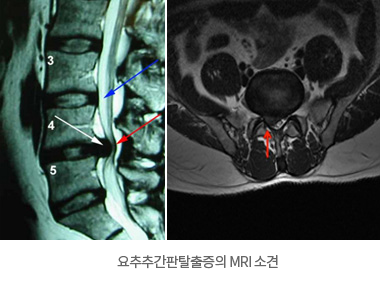

- └ 허리 디스크(요추 추간판 탈출증)

허리 디스크